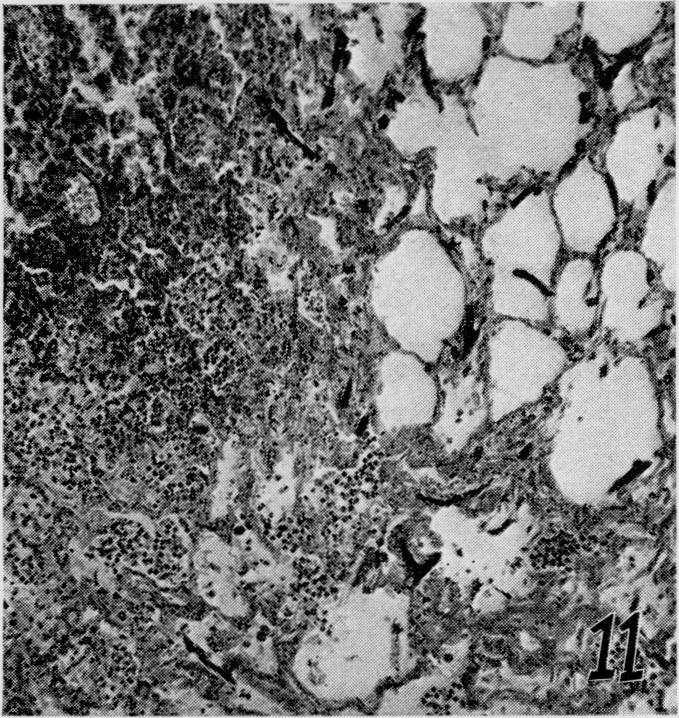

The effects of metabolic alterations on experimental Rhizopus oryzae (mucormycosis) infection.

Yale J Biol Med. 1956 Sep;29(1):23-32.